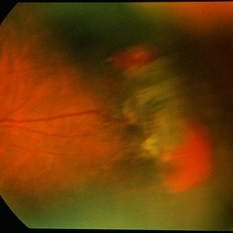

Sickle cell retinopathy (Proliferative) (2 files)

Sickle cell retinopathy (Proliferative) (2 files)

Proliferative sickle retinopathy (1 file)

Proliferative sickle retinopathy (1 file)

Proliferative Sickle Cell Retinopathy (Stage3) (10 files)

Proliferative Sickle Cell Retinopathy (Stage3) (10 files)

Sickle Cell Retinopathy (11 files)

Sickle Cell Retinopathy (11 files)

Sickle Cell Retinopathy SC (6 files)

Sickle Cell Retinopathy SC (6 files)

Sickle Cell (1 file)